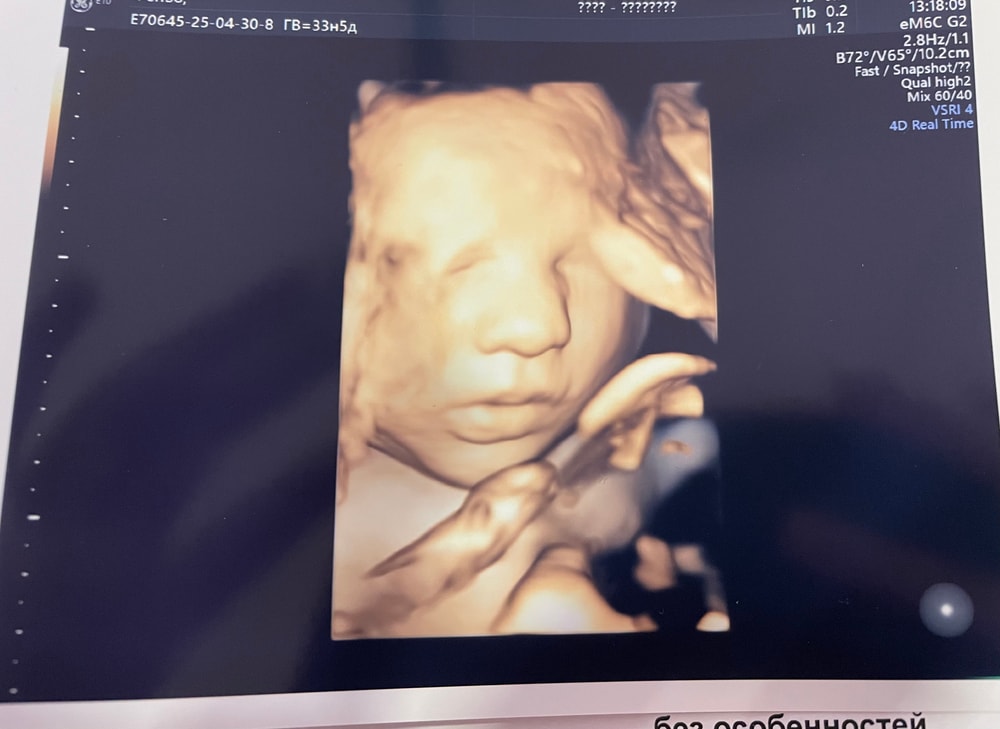

3 скрининг моего мальчика 🩵 33 нед 5 дней

Все хорошо у нас, сняли даже 3Д)))малыш и позевал, и язык показал, и улыбнулся 🥰Вес 2225гр, БР 82мм, ОЖ 298мм, БК 64,5мм, ЛЗР 110мм, ОГ 304мм, ПК 56мм, ИАЖ 15,9см.

Плацента по передней, высоко. Толщина 24мм.